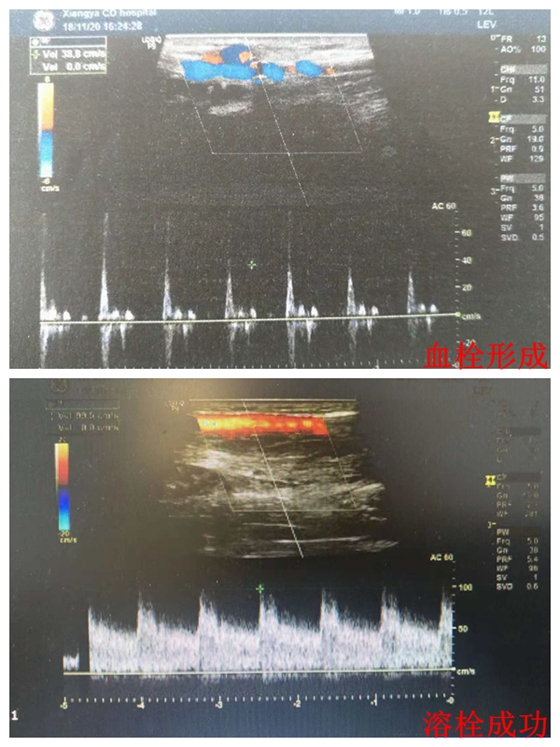

肾内科成小苗主任接诊后,考虑内瘘处有血栓形成,立即给患者行血管彩超检查也证实了内瘘处存在血栓,但此时血栓形成超过24h,已错过最佳溶栓时机。成小苗教授考虑到病情紧急,且仍有溶栓成功可能。在征得患者及家属同意后立即为患者办理住院,同时迅速组织党智杰主治医生,孙咏梅护士长及肖丽护士长组成的医护团队实施预定溶栓方案。虽然已经到了下班时间,肾内科医护团队依靠血管超声顺利定位血栓部位,及时为患者闭塞的内瘘进行局部精准溶栓治疗。当晚8时溶栓成功,内瘘处震颤明显,听诊杂音响亮。从患者办理住院到溶栓成功仅用2小时,保住了这位患者的“生命线”,并且得到了患者及家属的高度评价。